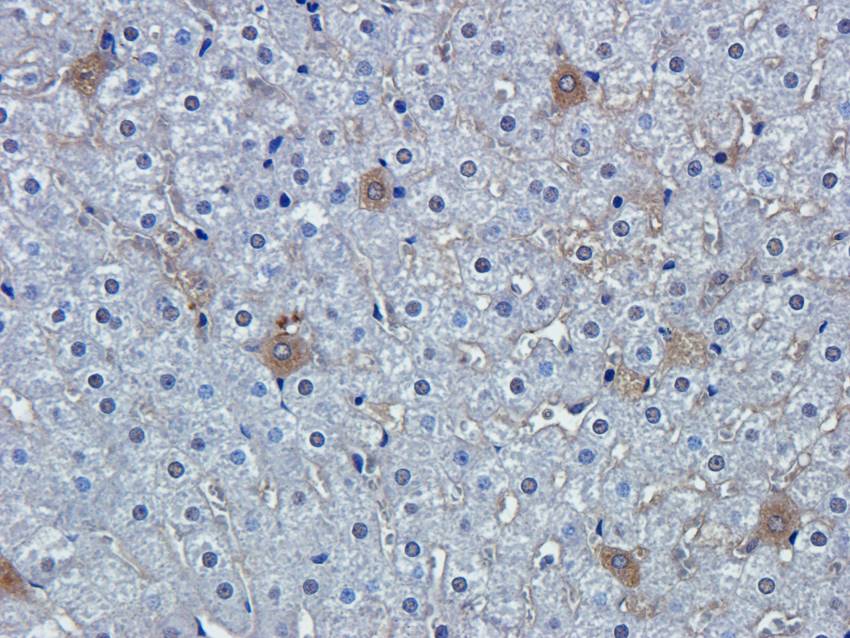

100 μg - PGP9.5 antibody [orb6713]Featured

ELISA, ICC, IF, IHC-P, WB

Human, Mouse, Rat

Rabbit

Polyclonal

Unconjugated

100 μg - FOXP3 antibody [orb34127]Featured